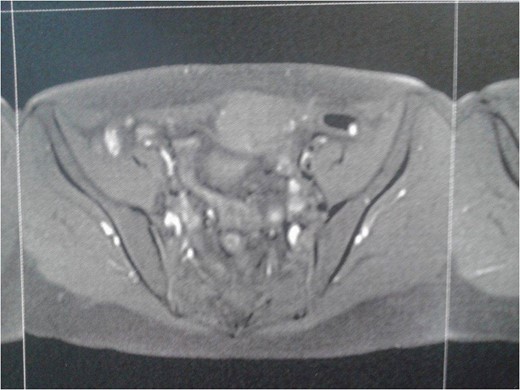

Complete blood laboratory tests, including tumor markers, showed values within normal limits. An abdominal computerized tomography and magnetic resonance imaging were performed; the latest revealed that the mass presented dimensions of 6.7 × 4.9 × 3.5 cm3, was located on the left rectus abdominis muscle, whereas no further intra-abdominal pathologic conditions were found (Figs 1 and 2). After adequate information and written consent, the patient was submitted to surgical excision of the mass.

A reoperation was considered necessary some days later, which included total hysterectomy, bilateral salpingo-oophorectomy, omentectomy and appendectomy. No signs of ascites, carcinomatosis, or ovarian abmormalities were present (Figs 5 and 6). Histology of all excised specimens did not reveal any ovarian or other malignancies, leading, thus, to the conclusion that the initial mass was a primary solitary serous peritoneal tumor. The patient was advised to perform a 6-month follow-up control, due to reported poor prognosis of the condition.